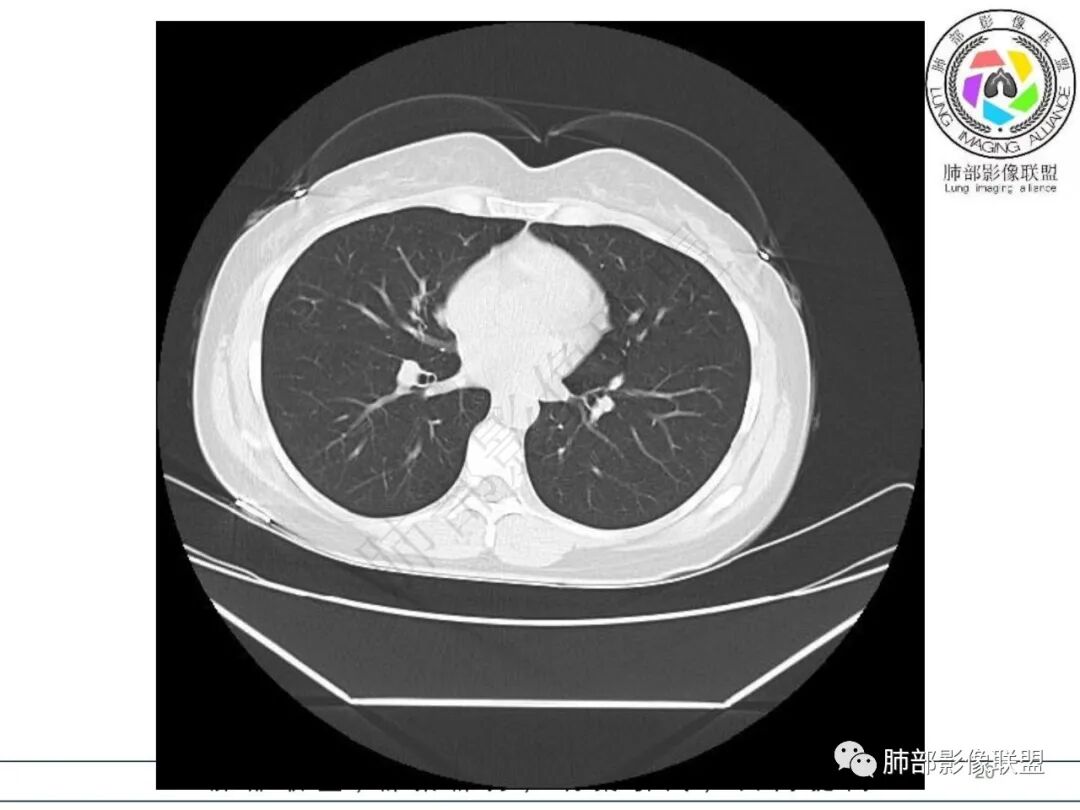

2.影像特征:右肺下叶局限性实变影伴晕征,边界不清,内部支气管尚通畅,实变区密实区边缘稍膨隆。符合炎性病灶特征。

3.综合分析:急性病程,炎性指标高,常见的是普通社区肺炎,如肺炎链球菌感染等。但本例患者临床表现较重,应先表现相对较轻,白细胞不高,须考虑非典型肺炎的可能性。本例隐球菌荚膜实验阴性,而军团菌临床症状一般较重,影像分布也更广泛、进展迅速,多器官损害更明显。因此考虑鹦鹉热衣原体可能性更大一些。其他如腺病毒等感染也是需要排除的。